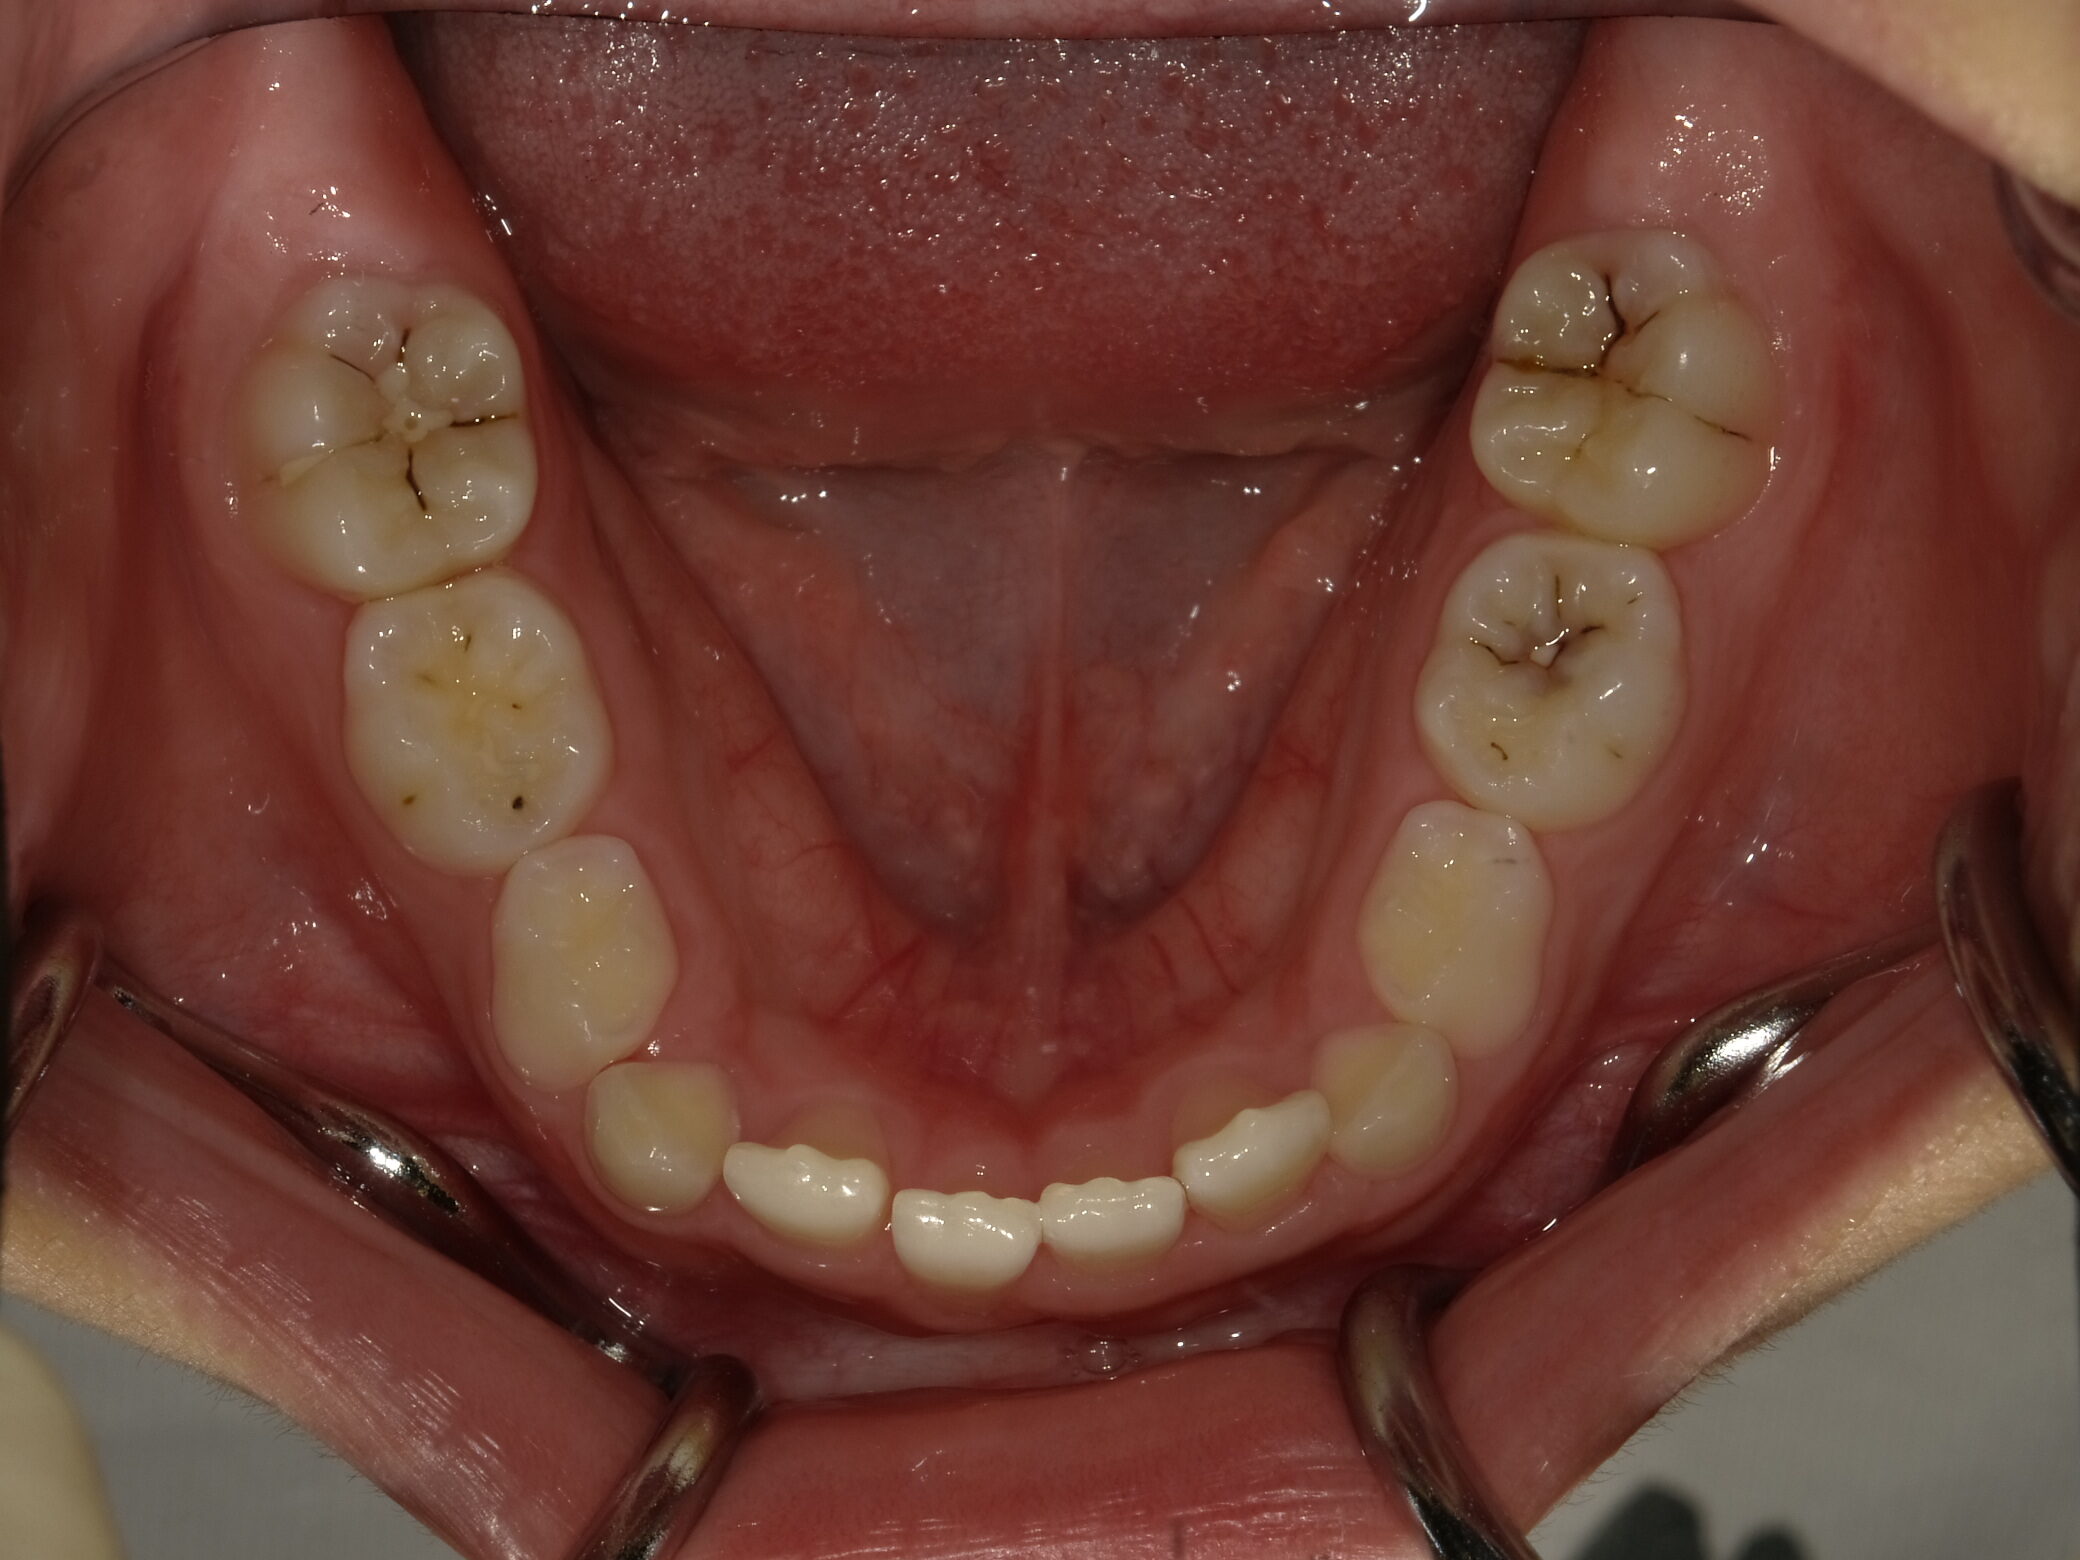

| 症例分類 | 交叉咬合 |

|---|---|

| 主訴 | 前歯がずれて咬んでいる |

| 年齢 | 9歳5ヶ月 |

| 性別 | 女性 |

| 抜歯部位 | なし |

| 使用装置 | 拡大装置、上顎前歯部のセクショナルアーチ装置、取り外し式保定装置 |

| 治療期間 | 1年2ヶ月 |

| 費用 | 相談料0円、検査料50,000円 動的矯正治療費330,000円 調整料6600円×15回分 保定装置料0円 |

| リスク・注意点 | 個々の歯の大きさに対して顎が小さく、歯が並ぶスペースが不足したために交叉咬合が生じています。これらを改善するために、幅の狭搾している歯列を側方に拡大した後、前歯を排列しました。

歯の動き方には個人差があり、予想された治療期間が延長する可能性があります。 治療中は矯正歯科装置が歯の表面に付いており、歯が磨きにくくなるため、むし歯や歯周病が生じるリスクが高まります。ハミガキを適切に行ってお口の中を常に清潔に保ち、さらに、かかりつけ歯科医に定期的に受診することが大切です。 矯正歯科装置の使用状況、定期的な通院など、矯正歯科治療には患者さんの協力が必要であり、それらが治療結果や治療期間に影響します。 治療の経過によっては当初予定していた治療計画を変更する可能性があります。 保定装置の装着時間が十分確保できない場合、歯並びや、咬み合せの「後戻り」が生じる可能性があります。 上下両側第二大臼歯の萌出を観察する必要があります。 |